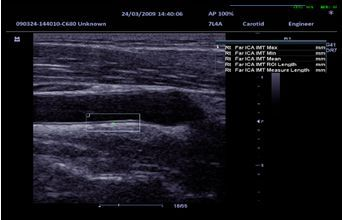

IMT (Толщина Интима-Медиа)

Автоматическое измерение толщины сосудистых стенок, обеспечивающее более точное исследование артерий.